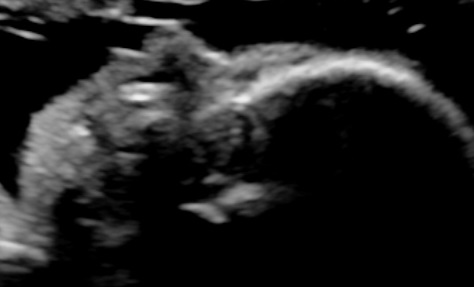

- Anatomy of the fetus and its movements should be examined carefully

- Doppler velocimetry of the middle cerebral artery to exclude fetal anemia